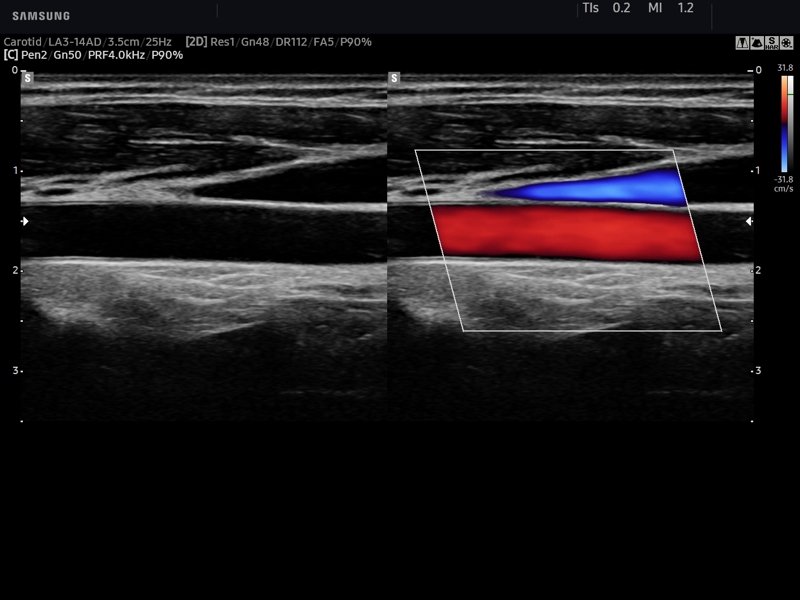

Общая сонная артерия, цветной доплер (эхограмма №747)

Изображение получено с помощью УЗ сканера HS60 (есть в продаже).